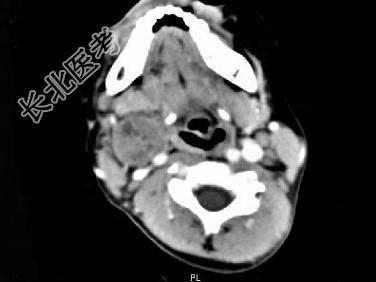

- 单项选择题女,4岁, 右侧颈部可扪及一包块约两个月,无热无痛, CT如图所示,最可能的诊断为 ( )

A、咽旁血管外皮瘤

B、咽旁副神经节瘤

C、咽旁脓肿

D、咽旁神经纤维瘤

E、咽旁小唾液腺混合瘤